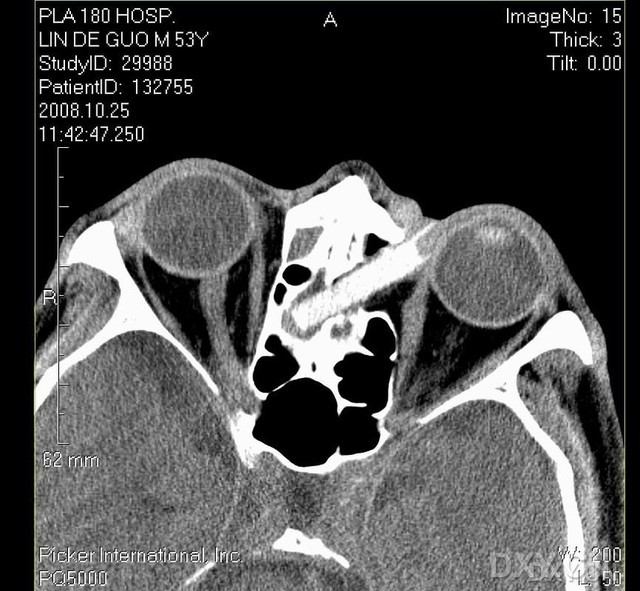

此次入住眼科后,考虑眼眶内有非磁性异物可能,经劝说(患者做了N次CT,不想再做了),行左眼眶CT平扫示:左眼内眦部及双侧筛窦区可见条状高密度影,大小约3.6cmX0.7cm,CT值138HU,边界清;左眼内眦部软组织稍肿胀,右侧筛窦、额窦窦腔密度增高、粘膜增厚(如图1)。初步诊断:左眼眶壁内异物。行左眼眶内异物取出术,术中按压溃疡区皮下感觉有毛刺状物,经扩大溃疡切口,见一尾部带毛刺的柱状物向内上方伸入左眼内上眶壁内,柱状物直径约0.5cm,类似竹制品,以血管嵌顺着异物方向用力缓慢拔出,发现异物实为一筷子断端,长约4cm,直径约0.5cm(图2),以1/1000庆大霉素生理盐水冲洗伤口后,放置引流管,缝合皮肤伤口。5天后拆线,溃疡痊愈,无眼部及头部不适。术后追问病史,患者始忆起3年前与人争斗时,对方手里拿有筷子,自己受伤昏倒后已记不清当时受伤情景。